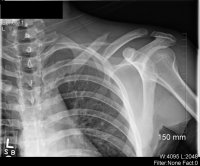

X-Rays:

Update: July 22, 2010

Well I saw the doctor today, the first time since surgery, and I got some new x-rays. Good news is that it's healing just fine and have great ROM. The bad news, I can't

for another 2 1/2-3 months.

The reason he gave is that the nature of the break is so bad that if I were to break it again before it's fully healed, it might not be repairable again. So I guess now I'm looking into October. Ugh :repeatablybangsheadagainstdesk: